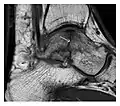

Figure 1: A 56-year-old woman presenting with left knee pain after a fall. (a) Initial anteroposterior radiograph was considered normal, however, subtle cortical disruption of the anterior rim of the medial tibial plateau, medial to the tibial spine, is noted (arrow). (b) Coronal T1-weighted MRI confirms the cortical disruption (arrow) and shows extensive fracture through the proximal tibia. (c) Coronal proton density-weighted image with fat saturation shows extensive edema in the subchondral bone. Note also hypersignal adjacent to the medial collateral ligament corresponding to a grade I sprain (arrowheads).[1]

High-energy trauma fractures

Occult osseous injuries may result from a direct blow to the bone by compressive forces of adjacent bones against one another or by traction forces during an avulsion injury. Lesions in the tibial plateau, hip, ankle, and wrist are often missed. In a tibial plateau fracture, any disruption of the posterior and anterior cortical rims of the plateau should be sought. Impaction of subchondral bone will appear as an increased sclerosis of the subchondral bone (Figure 1). In the hip, posterior acetabular fractures also present subtle radiographic findings. The acetabular lines should then be carefully examined keeping in mind that the posterior rim, which is harder to see on X-rays, is more frequently fractured than the anterior rim (Figure 2). In the wrist, detection of carpal bone fractures is often challenging, with up to 18% of scaphoid fractures radiographically occult. Carpal fractures, especially the scaphoid, are associated with the risk of avascular necrosis. In apparently normal wrist radiographs from symptomatic patients, if there is history of a fall on an outstretched hand with pain in the anatomic snuffbox, suggesting scaphoid injury, the initial examination with posteroanterior, lateral, and pronation oblique views must be complemented by other specific views such as supination oblique and the "scaphoid" view A careful examination of cortices for evidence of discontinuity or offset and cancellous bone for lucency is necessary (Figure 3).[1]